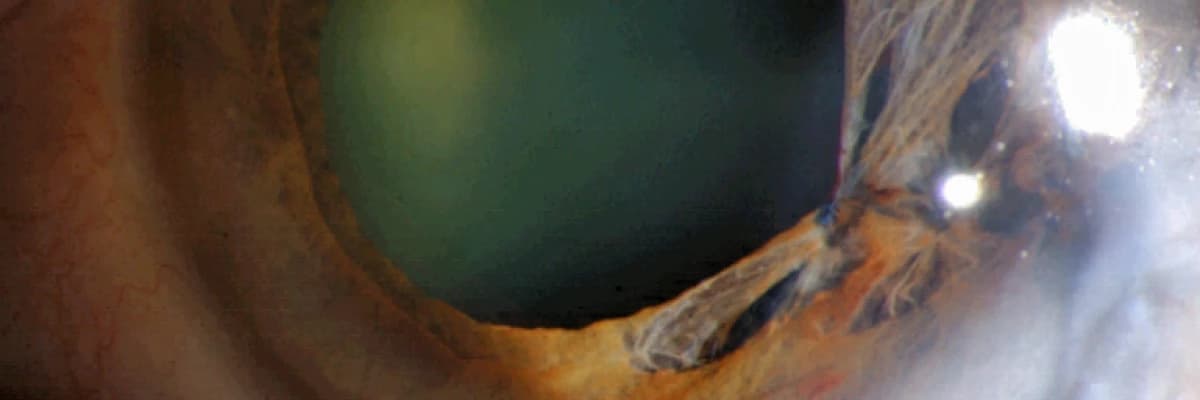

Gözbebeğinin işlevini veya şeklini düzeltmek ya da değiştirmek için uygulanan cerrahi bir müdahaledir. Genellikle;herhangi bir travmadan sonra oluşan deformasyonu onarmak için yapılır.

Gözbebeği aracılığıyla ışık;göz içine geçer ve dairesel bir yüzük gibi olan; ince bir göz kasıdır. Bu özel cerrahi işlem;10.0 prolin dikiş ile yapılır. Uygulanan bu yöntem "Pupilloplasti"olarak adlandırılır.

Pupilloplasti; çoğunlukla travmatik hasar gören veya çeşitli nedenlerle fonksiyonunu kaybeden gözbebeğinin; yeniden işlevini kazanması için uygulanmaktadır. Hasarlı ya da tam işlevsel olmayan gözbebeğindeki yetersizlik, bu operasyonla düzeltilir. Cerrahi onarımın en önemli yararı,göz içine giren ışık miktarını ayarlamak ve düzgün bir görme fonksiyonu yaratmaktır.